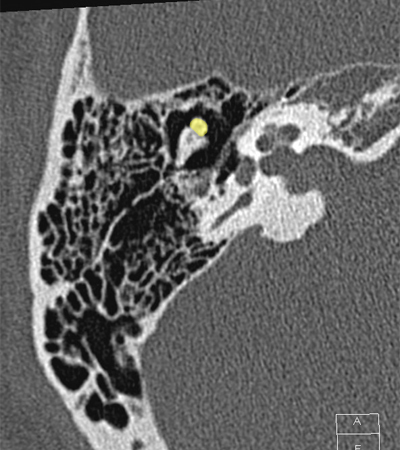

Cochlea Internal auditory canal Vestibule Posterior semicircular canal Head of malleus Body of incus Incudomallear joint

Radioanatomy of Temporal bone